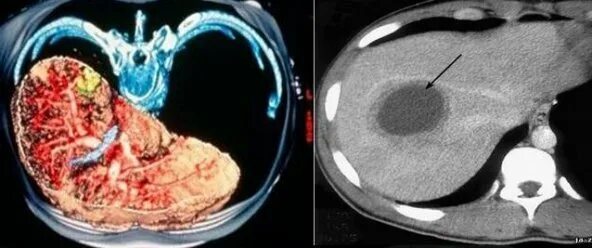

Подготовка к мрт печени